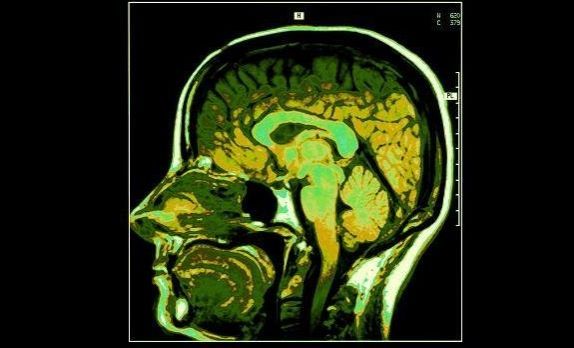

无题性能功效 https://so1.360tres.com/dmtfd/352_422_/t012e158ccad8adfaf4.jpg 吐真剂 1、麻醉分析为了让嫌犯处于镇静催眠状态中下意识地回答各种问题,在审讯过程中被多次使用。印度孟买之前发生过一起数百人伤亡的连环恐怖袭击案,为了从唯一被活捉的恐怖分子口中获取真实情报,印度警方对其使用了“吐真剂”,并成功获取了一份长达7页的审讯笔录。印度警方还用这种方法“解决”了不少棘手案件。 2、研究者研究后发现使用“吐真剂”后,嫌犯所“吐”的并非全是真话。 3、吐真剂让人处于镇静催眠状态中下意识地回答各种问题,但是麻烦之处在于,人有主观意识、潜意识、无意识三个层次。当主观意识被压抑到最大程度时,潜意识成为主导反应的行为中枢,会出现很多诡异的现象,比如幻觉;在这种状态下提供的信息并非完全的事实之全貌,而可能存在潜意识的夸张或者部分省略,而且回答者极易受到询问者的暗示和影响。 4、吐真剂对于那些有精神疾患的人群完全无效,因为精神疾患者出现的幻听幻视和虚构记忆,主要是大脑病变引起,因此他们自身对这部分“假话”深信不疑。

无题科学实验 https://so1.360tres.com/dmtfd/303_303_/t017c3a486b7a435bf7.jpg 吐真剂 “这是吐真剂——一种叫你说实话的药剂,效果奇强,只要三滴,就能使你透露出内心深处的秘密。”任课教师斯内普在课堂上从他的黑袍子中掏出了一只小小的水晶瓶,指着其中清澈的药水对哈利说。他威胁哈利,要不是魔法部严格限制吐真剂的使用,他就非把它悄悄倒进哈利的晚餐南瓜汁中不可。 当坏人拒不交代其罪行甚至狡猾地编造谎言时,公安人员只好动用测谎器。这是根据人在某种情绪状况(如惶恐、内疚、对抗)时,由于主神经作用而引起生理变化的原理设计的一种电子仪器。所谓生理变化,指的是血压变化、呼吸状态变化、皮肤电反应以及汗液分泌等变化。比如,受审者说谎时手心出汗增多,测谎器对此会有敏感性反应。但这种测谎器也有局限性。如果犯罪者心理素质特好,说谎也能做到面不改色心不跳、手心不出汗、血压不升高,那么测谎器的数据就会失真,因而也就无法判断他所述是否谎言了。

无题禁止使用 https://so1.360tres.com/dmtfd/400_225_/t01eab6ac8be1c82c41.jpg 吐真剂 印度最高法院的这项判决剥夺了警方以及调查员历来经常使用的一个工具。 印度首席法官巴拉克里斯南(K G Balakrishnan)表示,让嫌犯使用静脉麻醉剂硫喷妥钠后进行问话的行为是违反宪法的,任何嫌疑都不应该被迫成为一个对自己不利的证人,以后测谎仪和大脑映射(brain mapping)法也都被视为非法行为。